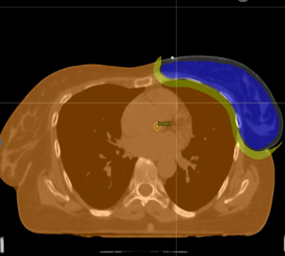

Case diagnosis:Left Breast Cancer

Treatment Site: Left breast with axilla and supraclavicular lymph nodes

Target: PTV_TOT_EVAL

Dose prescription: 50.0 Gy in 25 fr.

Techniques: 3D-CRT, IMRT, VMAT